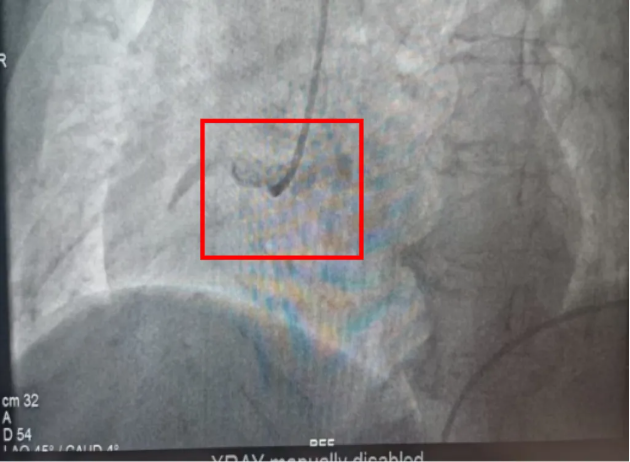

09:48,救护车呼啸着冲进宜宾市第五人民医院医共体总院大门,早已等候的医护人员立即给予口服心梗一包药;10:01复查心电图显示明显动态演变;10:09患者进入导管室;10:14,造影显示右冠状动脉近段完全闭塞,与心电图诊断完全一致。心内科团队随即熟练地植入一枚支架,开通血管。